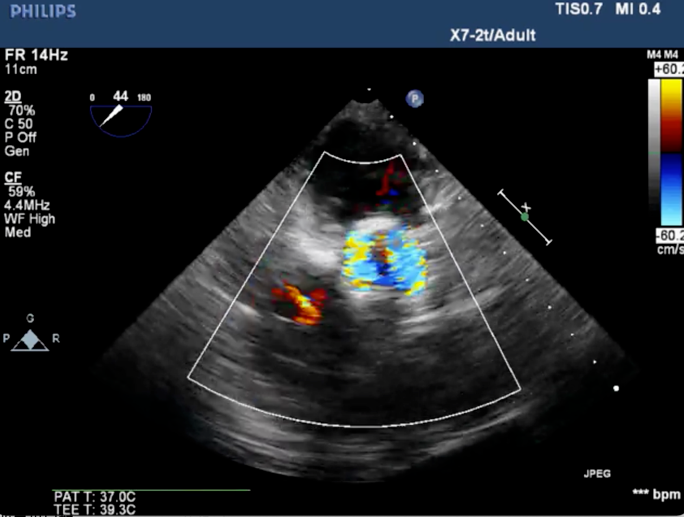

4、术后心电监护未见传导阻滞,心超提示人工主动脉瓣工作良好,瓣叶启闭正常,主动脉瓣峰值流速2 m/s,平均跨瓣压差6 mmHg,轻度瓣周漏。

主动脉根部造影示瓣膜位置合适(深度2 mm),轻度瓣周漏。遂释放瓣膜,撤回脑?;ぷ爸?,手术圆满成功。